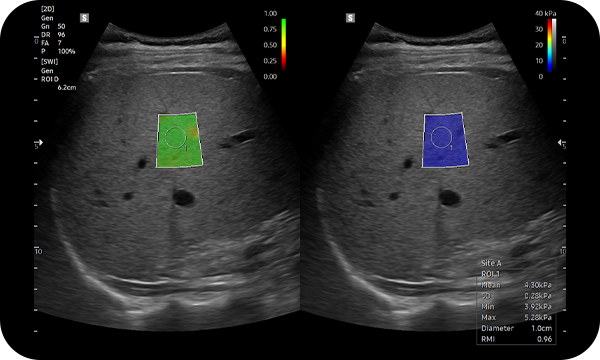

• Elastography is a non-invasive imaging test that measures the stiffness (elasticity) of the liver. Applied by ultrasound, it detects scarring (fibrosis) or fat accumulation.

• Results from elastography provide two important pieces of information:

• Fat content (steatosis) — how much fat is deposited in the liver cells

• Fibrosis / stiffness — how much scarring or irreversible tissue damage has occurred